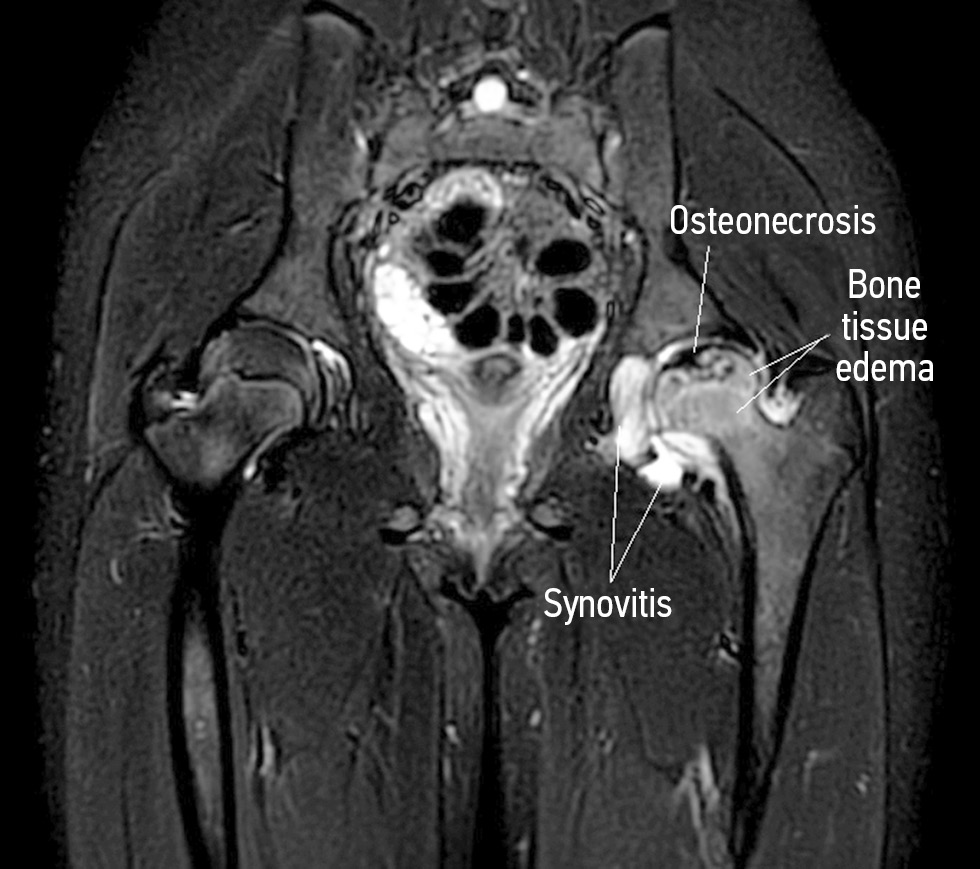

Тяжесть поражения головки бедренной кости оценивали по объему очага некроза и интенсивности трабекулярного отека прилежащих отделов костной ткани и выражали в балах, где 0 — отсутствие очага некроза и трабекулярного отека; 1 — объем очага некроза и зона трабекулярного отека занимают не более 33 % эпифиза; 2 — объем очага некроза и зона отека занимают 34–66 % эпифиза; 3 — объем очага некроза и зона отека занимают 67–100 % эпифиза (рис. 3). Таким образом, максимальное суммарное число балов — 6. Считалось, что остеоартрит с высокой степенью активности соответствует 5–6 баллам, умеренной активности — 3–4 баллам, низкой активностью — 2 баллам. Неактивная стадия остеоартрита у детей соответствует 0–1 баллу при условии отсутствия очага некроза (рис. 4). Лабораторный комплекс включал определение значений стандартных маркеров воспалительной активности и костного метаболизма, а также уровень кальпротектина, виментина, интерлейкина-6 (IL6), фактора некроза опухоли альфа (TNF-α) в сыворотке крови, титра антинуклеарного фактора (АНФ) на клеточной линии HEp-2 на момент верификации остеоартрита. Всем детям также проводили тестирование на наличие антифосфолипидного синдрома и гипергомоцистеинемии.

Рис. 3. Магнитно-резонансная томограмма: признаки различной тяжести поражения головки бедренной кости у детей с болезнью Легга – Кальве – Пертеса. На магнитно-резонансной томограмме в режимах STIR представлены: объем очага некроза и зона трабекулярного отека занимают не более 33 % эпифиза (а); объем очага некроза и зона отека занимают 34–66 % эпифиза (б); объем очага некроза и зона отека занимают 67–100 % эпифиза (в, г)